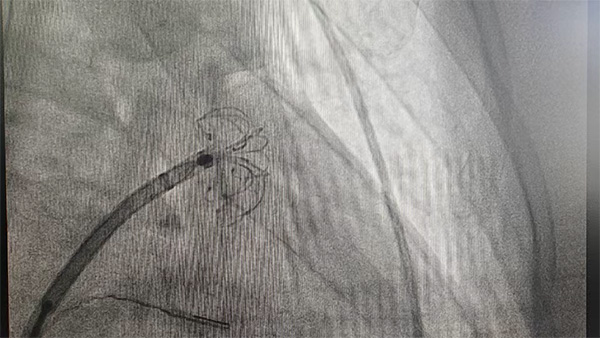

植入:采用渐进式的方式植入封堵器,过程中遇到了一定的困难,固定盘下缘进入心耳后整个盘无法完全展开,在保证固定盘展开的情况下无法将其送入心耳;考虑原因为伞盘过大,决定更换封堵器。

植入过程:通过渐进式植入固定盘,在右肩位及肝位确定固定盘抵达预定位置且完全展开。